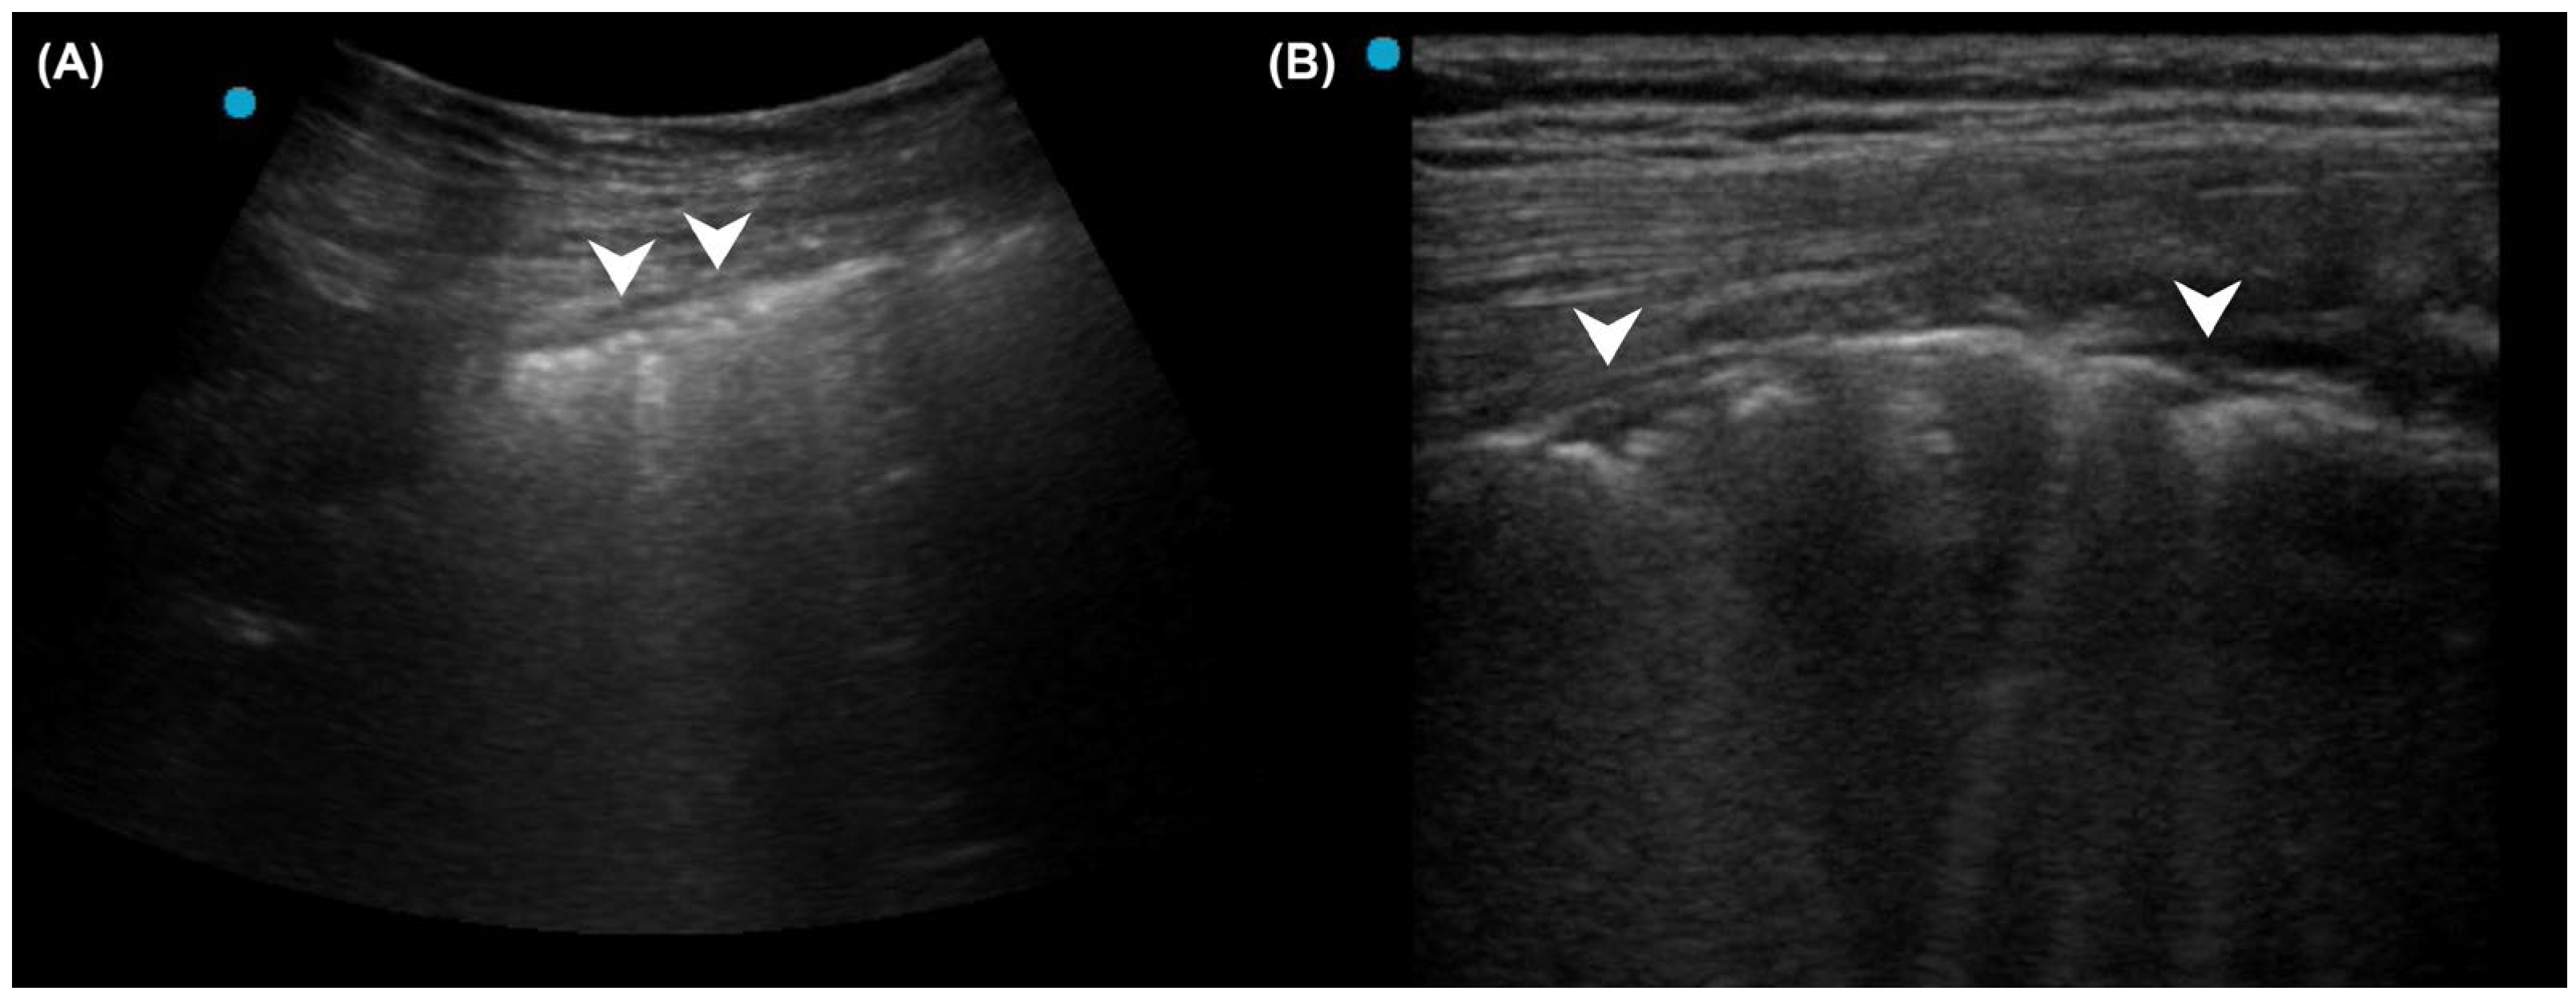

- Lichtenstein, D.; Mezière, G.; Seitz, J. The dynamic air bronchogram. A lung ultrasound sign of alveolar consolidation ruling out atelectasis. Chest 2009, 135, 1421–1425. [Google Scholar] [CrossRef]

- Lichtenstein, D.A.; Lascols, N.; Prin, S.; Mezière, G. The “lung pulse”: An early ultrasound sign of complete atelectasis. Intensive Care Med. 2003, 29, 2187–2192. [Google Scholar] [CrossRef] [PubMed]

- Liu, J.; Chen, S.W.; Liu, F.; Li, Q.P.; Kong, X.Y.; Feng, Z.C. The diagnosis of neonatal pulmonary atelectasis using lung ultrasonography. Chest 2015, 147, 1013–1019. [Google Scholar] [CrossRef]